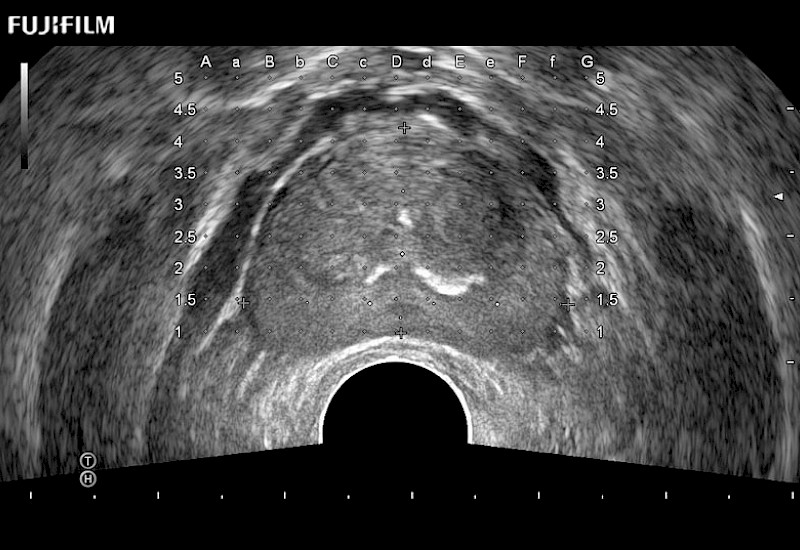

Exclusive 200° FOV end-fire prostate biopsy transducer.

Main Specifications:

Provides real-time imaging of both the sagittal and transverse planes